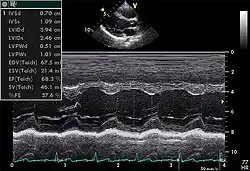

Echocardiogram in the parasternal long-axis view, showing a measurement of the heart's left ventricle

Motion mode is infrequently used in modern echocardiography. It has specific uses and has the benefit of very high temporal fidelity (eg, measuring LV size at end diastole).